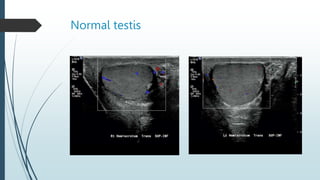

Ultrasound

The normal testes have a homogeneous,

moderately echogenic pattern.

 A testis is surrounded by a thin echogenic

fibrous band, which represents the visceral

component of the tunica vaginalis and the tunica

albuginea.

 In the absence of intrascrotal fluid, the tunica is

usually visualized only at its hilum as an

echogenic structure, where it invaginates into the

testis, to form the mediastinum testis.

Normal testis.

Normal testis